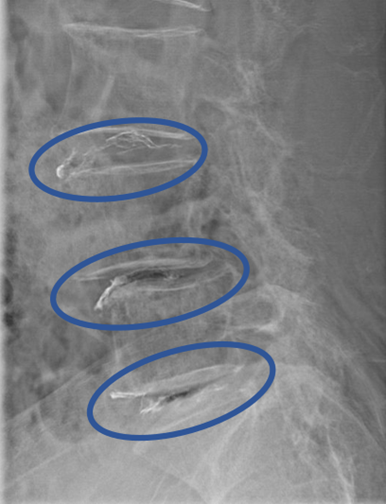

DiscoGelを入れた後の画像になります。

治療は 30分程度で終了

回復室で休憩後、歩いて帰院されました。